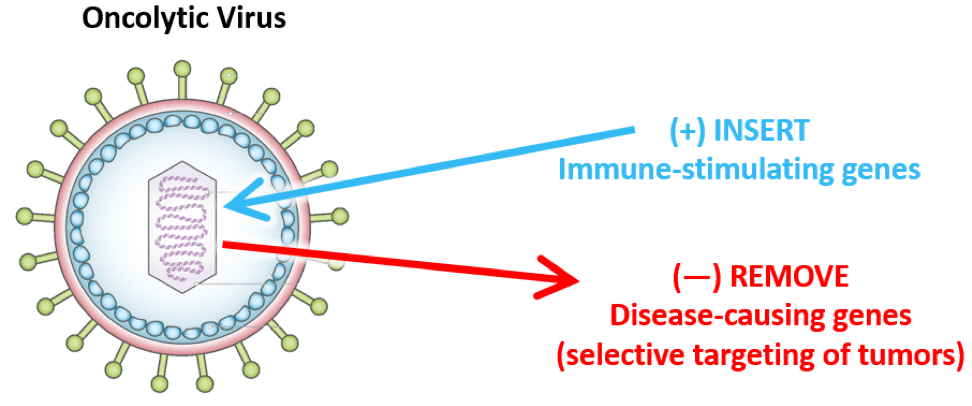

- 精 总缓解率达69%!硼中子疗法成为对抗癌细胞的“秘密武器”

- 精 肿瘤缩小86%!关于硼中子疗法你了解多少?